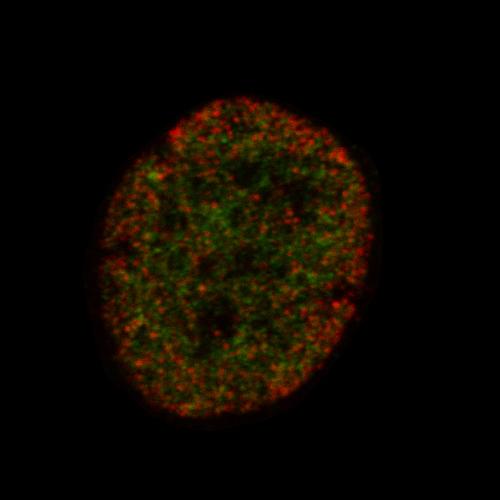

To identify earlier signals of a stem cell's fate, an interdisciplinary team from multiple universities collaborated to use super-resolution microscopy to analyze epigenetic modifications. Epigenetic modifications change how DNA is wrapped up within the nucleus, allowing different genes to be expressed. Some modifications signal that a stem cell is transitioning into a particular type of cell, such as a blood, bone or fat cell. Using the new method, the team of scientists was able to determine a cell's fate days before other techniques.

The approach, called EDICTS (Epi-mark Descriptor Imaging of Cell Transitional States), involves labeling epigenetic modifications and then imaging the cells with super resolution to see the precise location of the marks.

The team demonstrated the method's capabilities by measuring two types of epigenetic modifications in the nuclei of human stem cells cultured in a dish. They added chemicals that coaxed some of the cells to become fat cells and others to become bone, while another set served as control. Within three days, the localization of the modifications varied in cells destined for different fates, two to four days before traditional methods could identify such differences between the cells. The technique had the specificity to look at regional changes within individual cells, while existing techniques can only measure total levels of modifications among the entire population of cells.